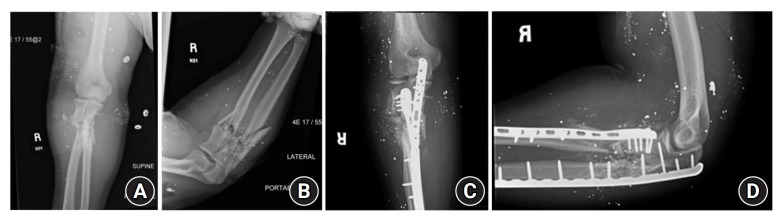

Results: Twenty-four patients were identified. All patients received prophylactic antibiotics upon admission and underwent urgent surgical debridement. Open reduction and internal fixation (ORIF) was performed with initial debridement in 22 of 24 patients. Seven patients sustained distal humerus fractures, 10 patients sustained isolated proximal ulna or proximal radius fractures, and seven had combined fracture patterns. Eleven patients presented with nerve palsy, and two had transected nerves. Two patients had vascular injury requiring repair. One patient required a temporary elbow-spanning external fixator and underwent staged debridement followed by ORIF. One patient with a grade IIIC fracture developed a deep infection that precluded ORIF. One patient required revision ORIF due to fracture displacement.

Abstract Image